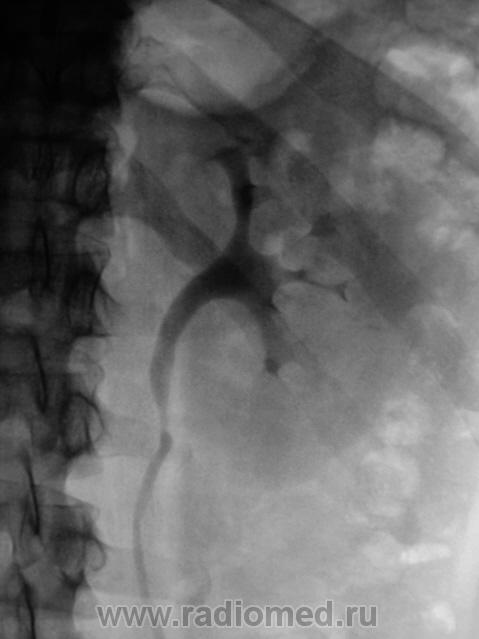

Р-признаки стриктуры верхней трети мочеточника с супрастенотическим расширением в виде  умеренной пиелокаликоэктазии левой почки.

уролит?

Камешек на уровне поперечного отроска L2.

А как насчёт добавочных сосудов?